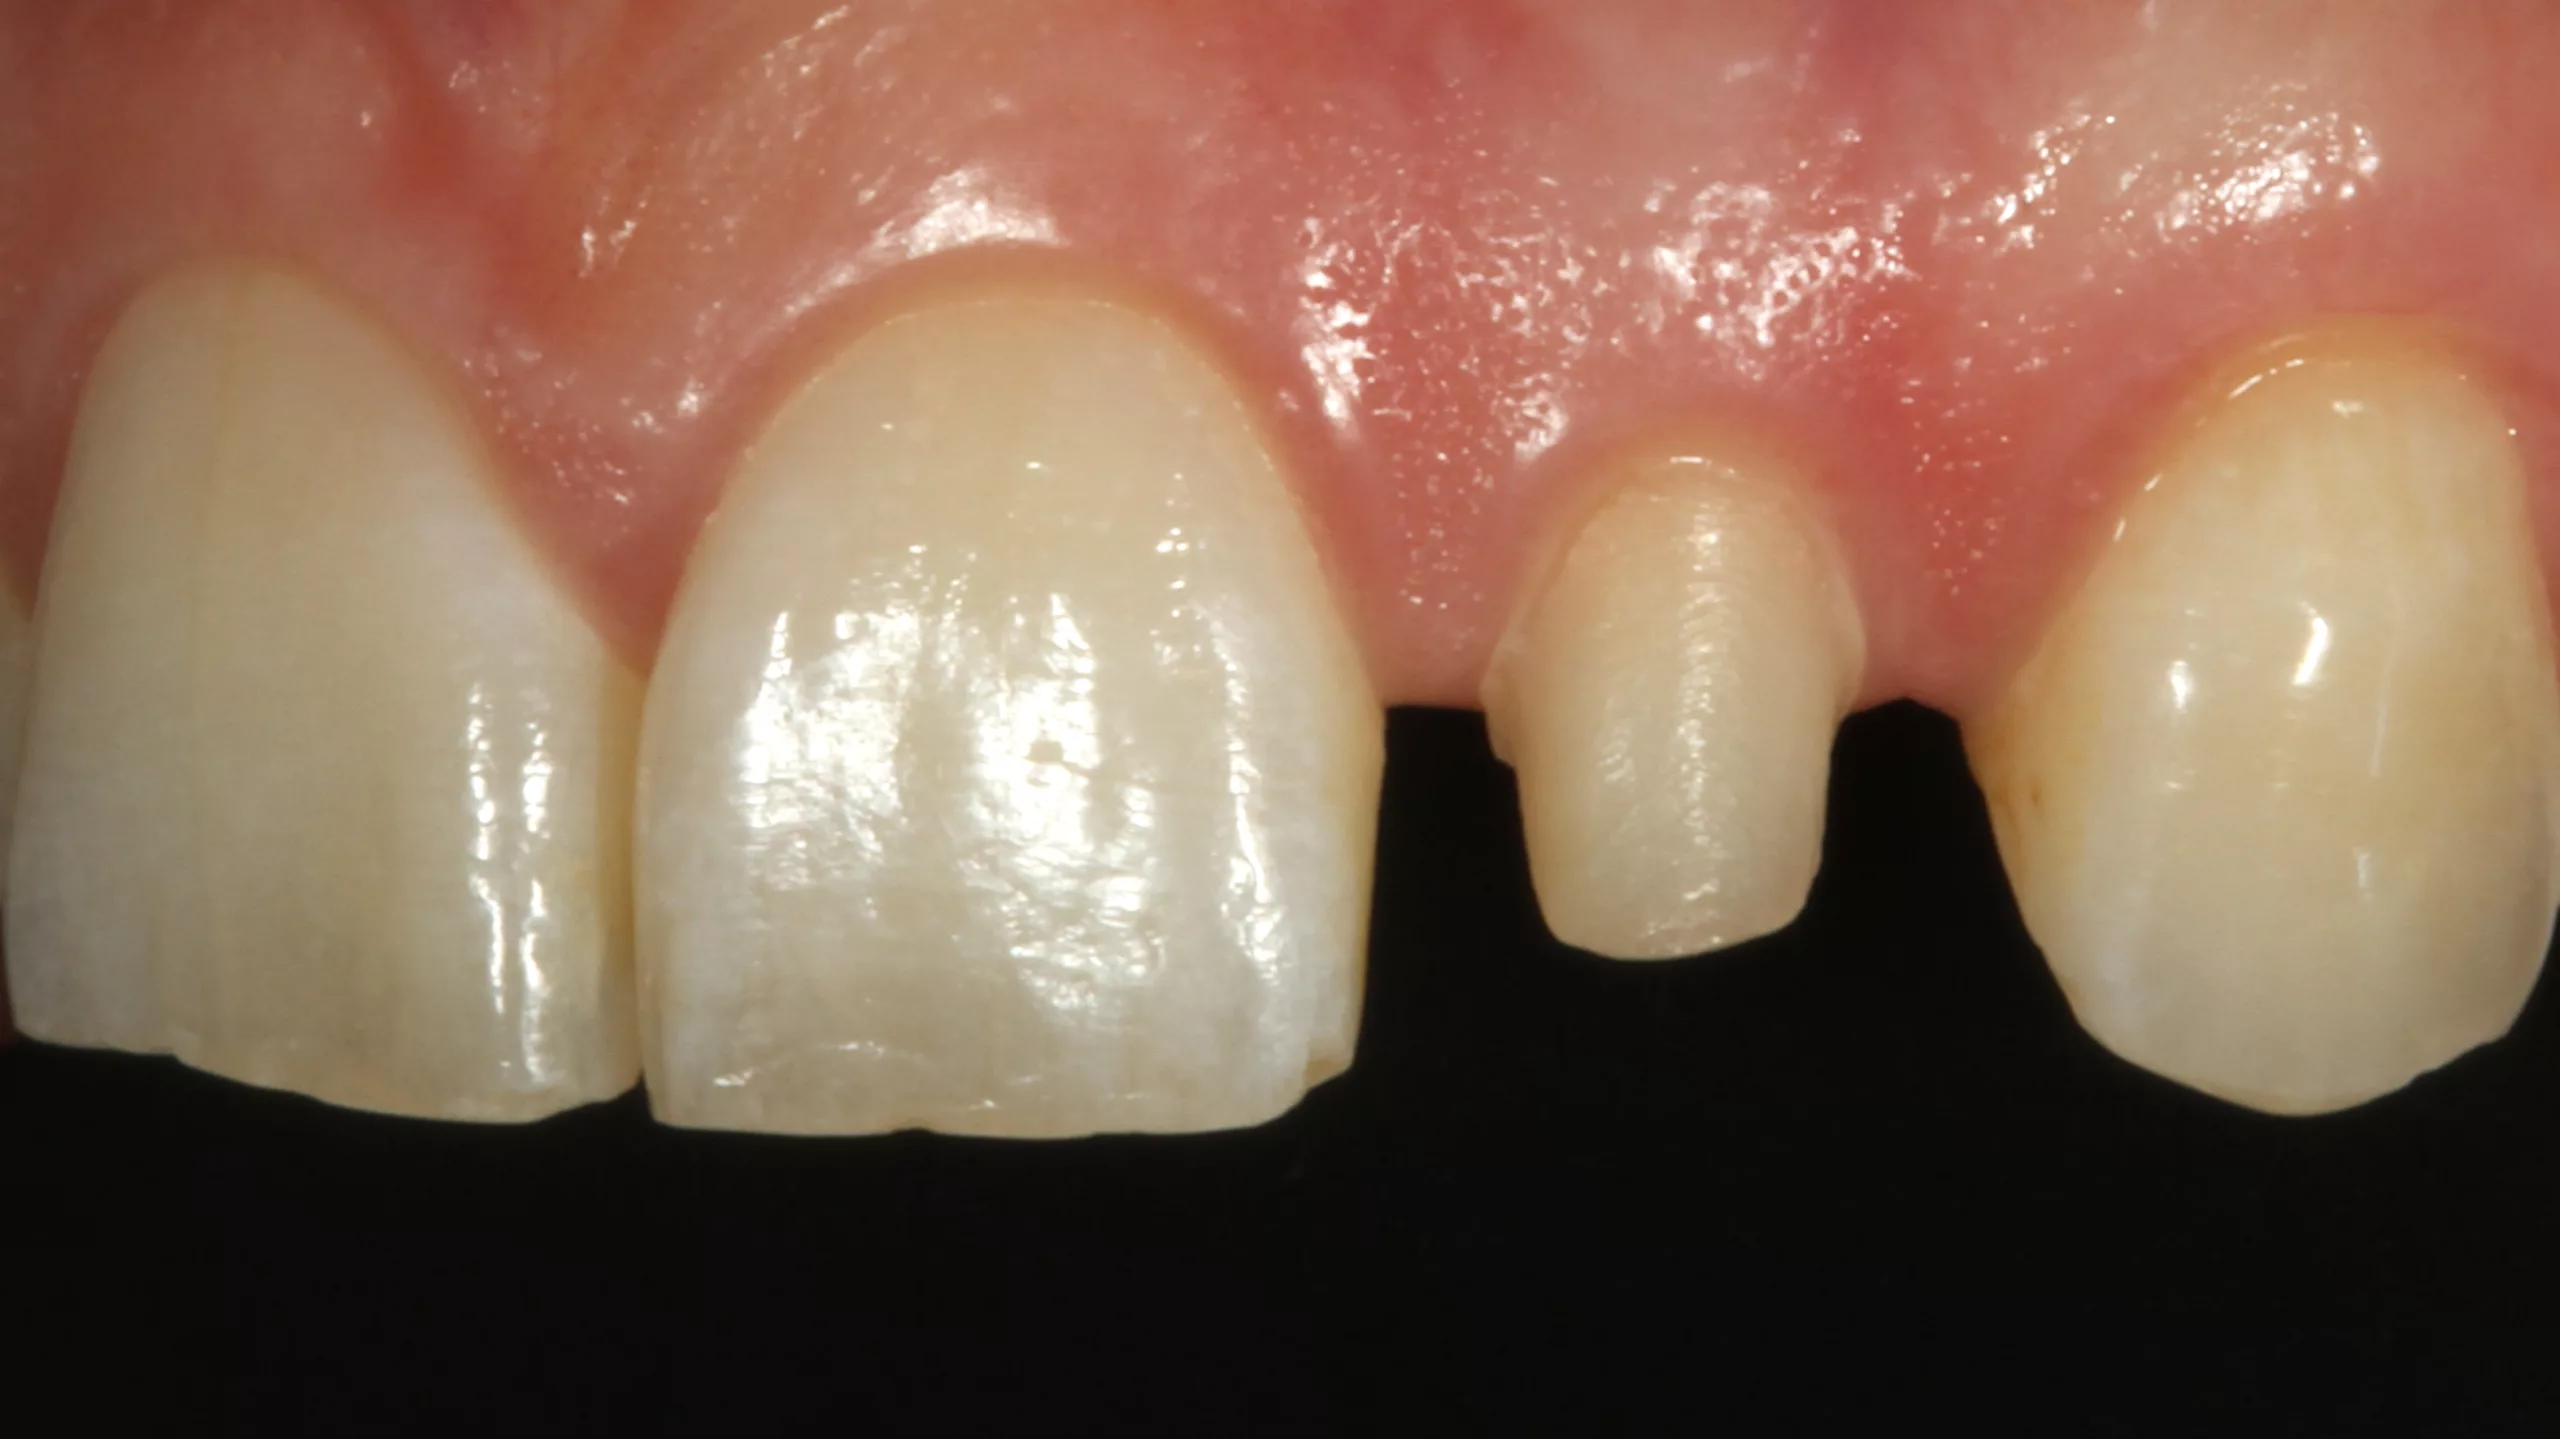

Die 32-jährige Patientin stellte sich mit einem komplett abgebrochenen, alio loco erstellten direkten Kompositaufbau an Zahn 22 vor (Abb. 10 und 11). Die beiden seitlichen Schneidezähne sind sehr kleine Zapfenzähne, deren ästhetische Verbreiterung vor einigen Jahren in direkter Technik vorgenommen worden war (Abb. 12). Aufgrund ihrer Press- und Knirschgewohnheiten mussten ihrer Angabe nach bereits mehrfach Ausbesserungsarbeiten vorgenommen werden. Die Vorpräparation ähnelte allerdings einer Veneerpräparation, sodass aufgrund der existierenden Vorpräparation und den erhöhten Anforderungen an die Stabilität im Beratungsgespräch eine indirekte Versorgungsform favorisiert wurde.

Direkte Frontzahnversorgungen mit Komposit funktionieren in der Regel hervorragend und sollten somit immer die 1. Wahl in der Überlegung alternativer Versorgungskonzepte darstellen. [6,31,37,55,58,59,62]. Es ist aber auch nicht zu unterschätzen, dass derartige Restaurationen sehr anspruchsvoll sein können [41,42]. Deswegen sind indirekte keramische Restaurationen – meist aus Glaskeramik – eine valide Alternative, wenn höchste ästhetische Ansprüche befriedigt werden müssen. [3,4,7,20,34, 40,43,44,57,65,89,98]. Ergibt allerdings eine Vorpräparation eine Ausgangssituation, die präparationstechnisch kaum verändert werden muss, und müssen erhöhte Anforderungen an die Bruchfestigkeit gestellt werden, ist eine indirekte Restauration die 1. Wahl, da keine weitere invasive Präparation erforderlich und eine bessere Langzeitprognose gegeben ist. So fiel die Entscheidung zugunsten einer labial verblendeten monolithischen Vollzirkonkrone (Abb. 13 und 14). Es wurde erwogen, Zahn 12, der mit einem vergleichbaren Kompositaufbau versorgt worden war, wie Zahn 22 mitzuversorgen. Da an dem Zahn 12 aber kein Akutereignis Berücksichtigung finden musste, verzichtete die Patientin auf diese zusätzliche Behandlungsoption. Bei der Formgestaltung wurde in Absprache mit der Patientin bewusst keine Rücksicht auf die jetzige Form von Zahn 12 genommen und eine symmetrische Versorgung bewusst ignoriert, um bei einer Neuversorgung von Zahn 12 in der Zukunft dann keine Formkompromisse eingehen zu müssen. Die Form der neugestalten seitlichen Schneidezahnkrone orientierte sich somit ausschließlich an den Zähnen 21 und 23 und den gegebenen vertikalen Dimensionen.